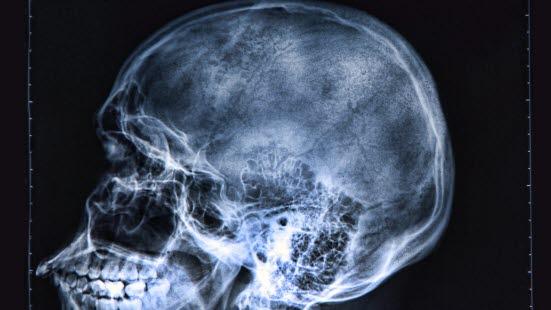

Skjelettet i hodet kalles for hodeskallen (kraniet). Hodeskallen består av to deler: hjerneskallen og ansiktsskjelettet.

Hjerneskallen har form omtrent som et egg og ligger rundt hjernen og høre- og likevektsorganet. Den består av et ”tak” og et ”gulv”.

”Taket” har en jevn krumning og består av en pannedel, en issedel, en bakhodedel og en tinningdel på hver side. Disse delene er festet til hverandre ved hjelp av ubevegelige ”ledd” som kalles suturer. Suturene likner sømmer slik at det kan se ut som om hjerneskallens flate knokler er ”sydd sammen”. Hos spedbarn har disse leddene en viss tøyelighet, noe som gjør at barnets hode under fødselen til en viss grad kan tilpasse seg fødselskanalen.

"Gulvet" i hjerneskallen har en mer uregelmessig form. Det består av mange hull hvor blodkar, nerver og ryggmargen trenger inn og ut gjennom skallen.

Ansiktsskjelettet støtter og beskytter ansiktets strukturer. Det består av overkjeveskjelettet, underkjeven og tungebenet. Overkjeveskjelettet består av 6 par ben og 1 uparet. De er gjennom suturer fast forbundet med hverandre og hjerneskallen.

I skallens ansiktsdel finnes begge øyehulene, den benete delen av nesen som er skilt fra munnhulen med en benplate. Overkjeveskjelettet rommer også bihulene. På siden av skallen finnes åpningen til ytre øregang. Like foran denne finnes kjeveleddet som er forbindelsen mellom tinningbenet og underkjeven.